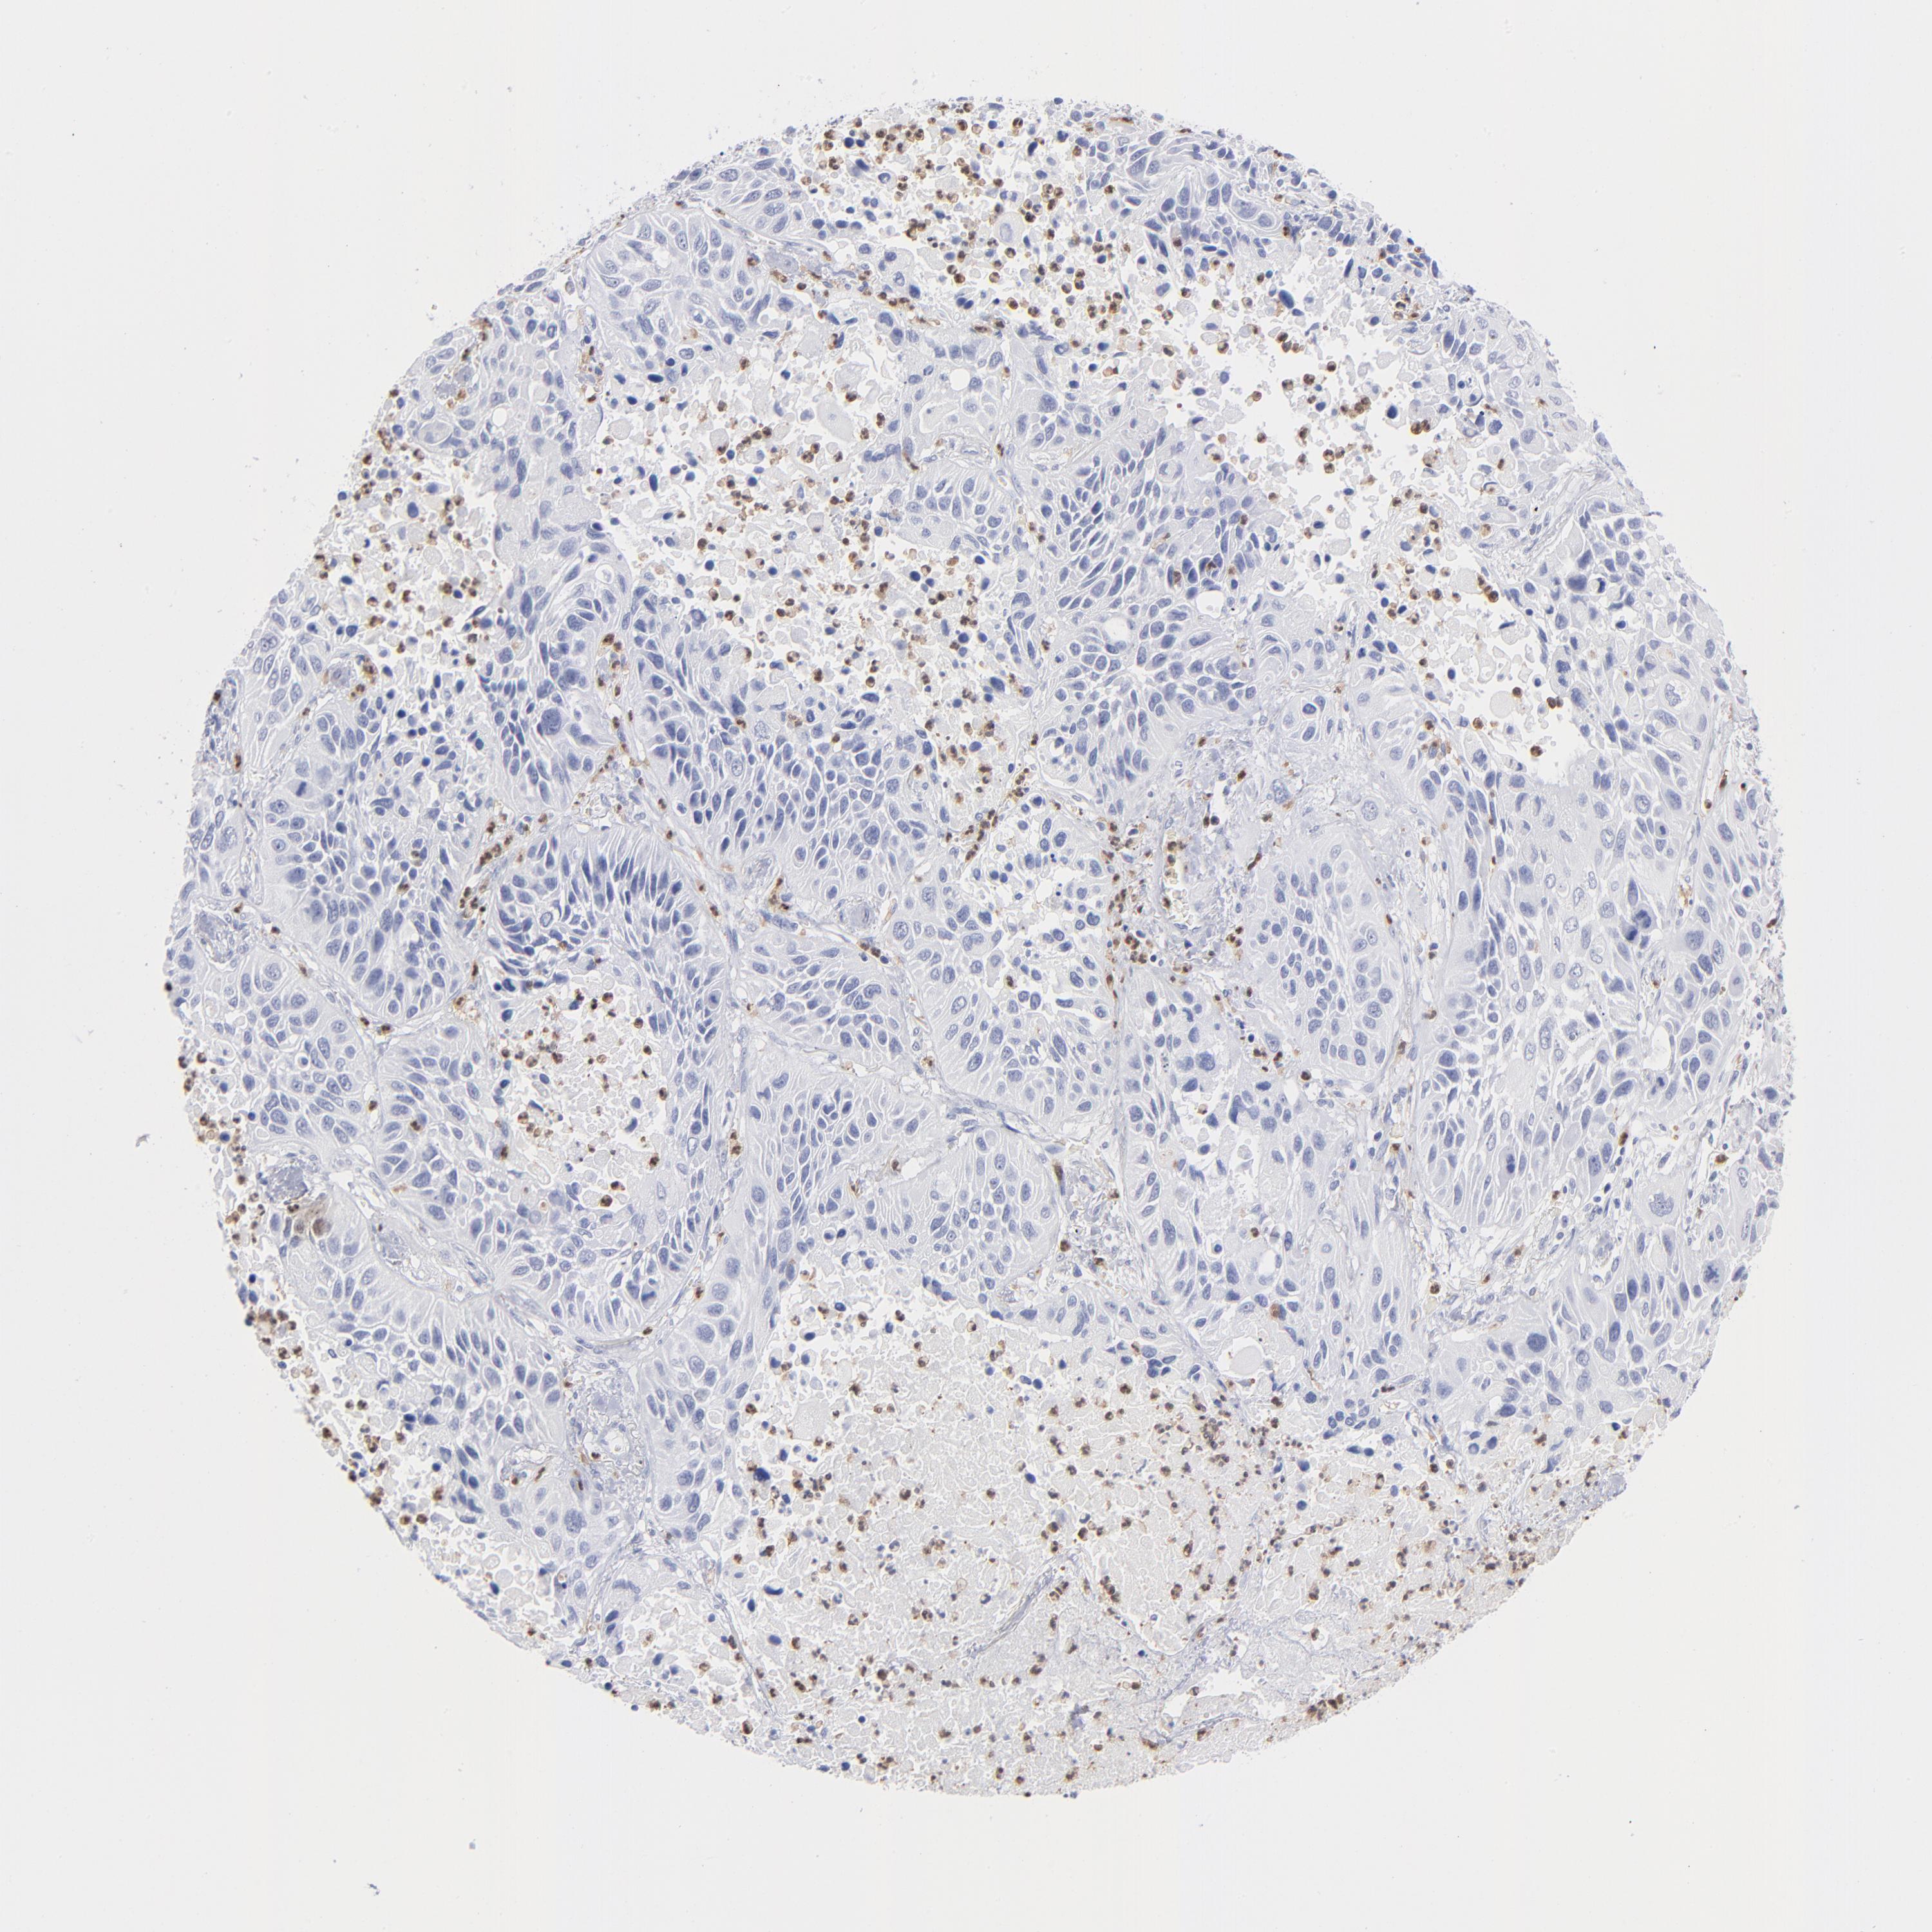

CANCER LUNG CANCER Show tissue menu

LUAD TCGA LUAD VALIDATION LUSC TCGA LUSC VALIDATION PROTEIN LUAD CPTAC PROTEIN LUSC CPTAC PROTEIN EXPRESSION

ANTIBODIES

AND

VALIDATION